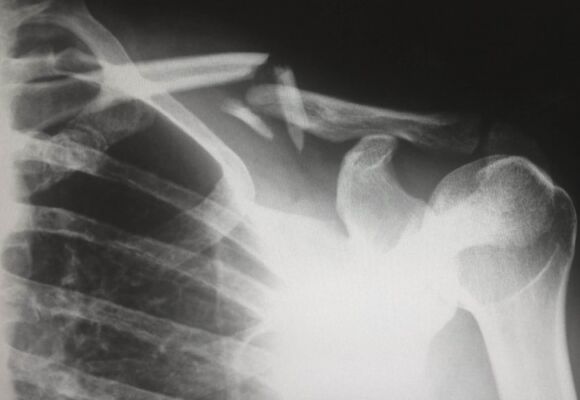

NBB Waldrons Solicitors have been contacted by a number of clients who have concerns about Mr Mian Munawar Shah, Consultant Orthopaedic Shoulder Surgeon at Walsall Manor Hospital. Concerns have been raised about the performance of shoulder operations at the hospital in Walsall, with several people left in a worse condition as a result of surgery. In some cases, surgery (or more complex surgery) has been carried out unnecessarily highlighting surgical negligence. Other patients have been told about problems with the placement of surgical screws and pins.

A number of his patients have experienced poor outcomes following surgery. The Trust have investigated the treatment provided by him and are said to be actively contacting his patients to review how they were treated and if there were any potential shoulder surgery negligence claims. Concerns have also been raised about operations being carried out unnecessarily, and in some cases complex surgery has been carried out when a simpler operation would have been more suitable. An example is the ‘Latarjet Procedure’.

The Latarjet procedure is a type of surgery carried out on the shoulder, and is named after a French surgeon. It is usually carried out to treat shoulder instability or recurrent shoulder dislocations. It often involves transferring the coracoid (part of the shoulder blade) with its attached muscles to the front of the glenoid (the socket portion of the shoulder joint). This provides additional bone to hold the head of the humerus (the bone in the upper arm) within the shoulder socket more securely.